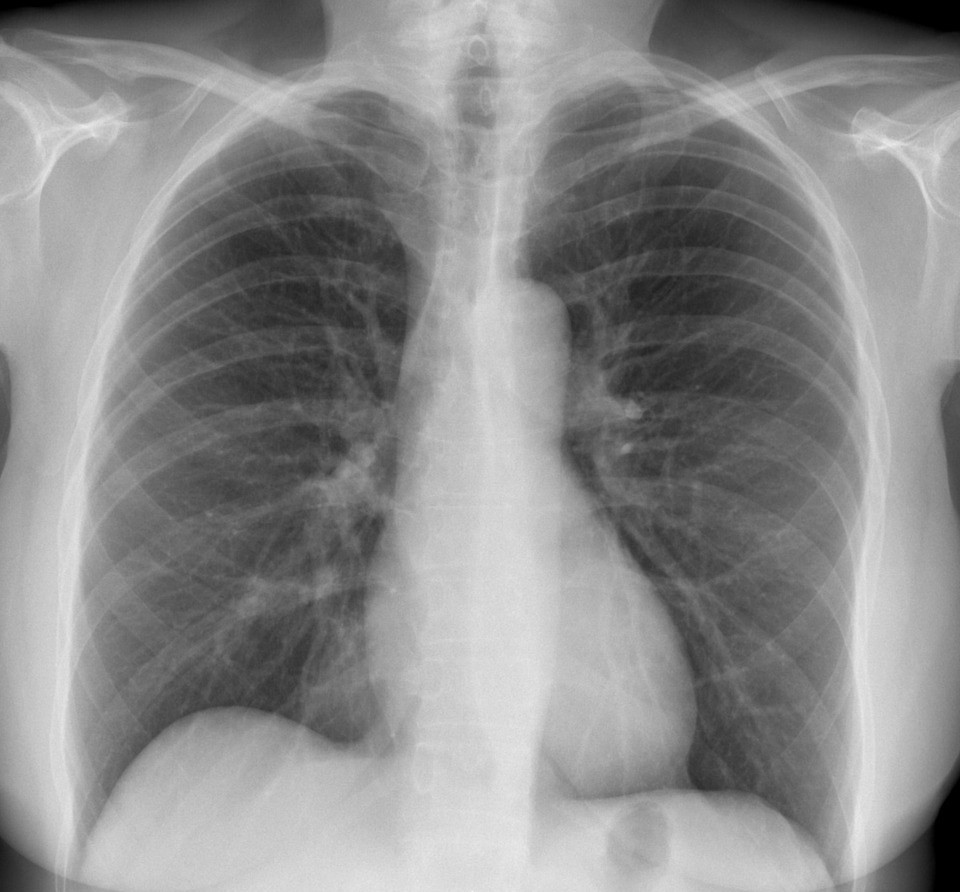

Radiografie cardio pulmonara viza australia 160 00 lei. Radiografie investigatie nedureroasa neinvaziva. Recomandare de la medicul de familie specialist buletin sau carte de identitate dotari aparat rtg duodiagnost philips aparat rtg polymibil aparat rtg transportix. O radiografie toracica ofera imagini ale inimii plamanilor cailor respiratorii vaselor de sange coloanei vertebrale si peretilor toracici.